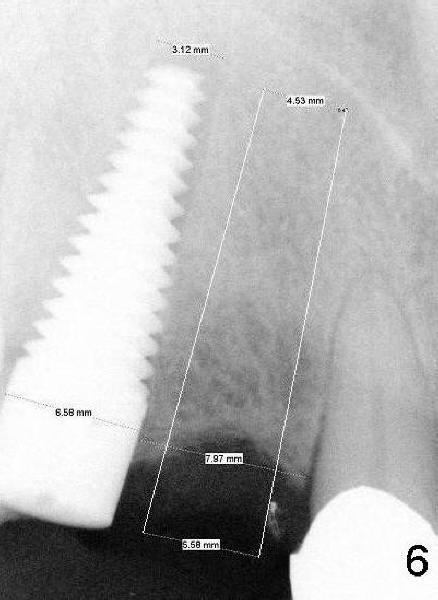

There is approximately 8 mm between the tooth #8 and the implant at the site of #6 (Fig.6,7). The distance appears to be enough to place D2 and D1 implants (Fig.6,7, respectively).